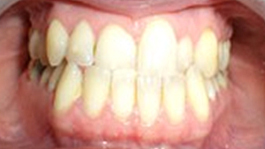

Présentation cas clinique :

Avant traitement

Après traitement